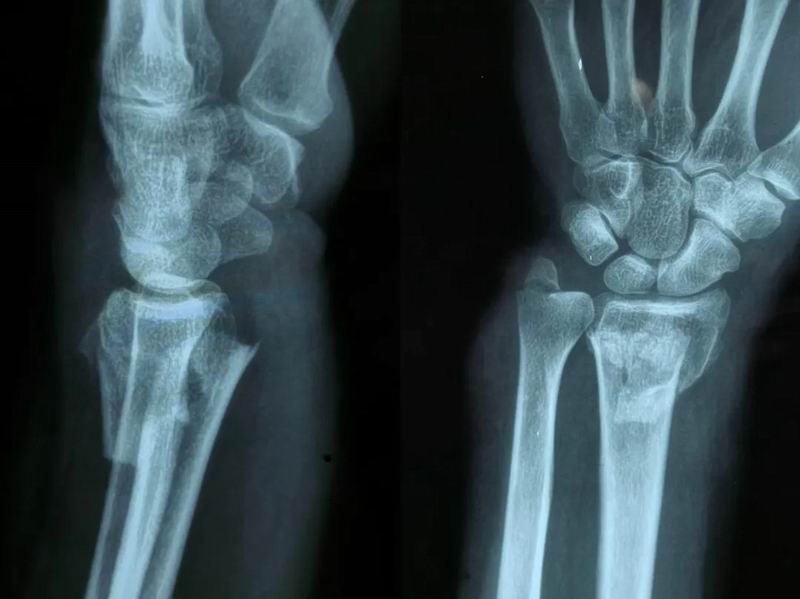

在日常生活中,当人们不慎跌倒时,通常会本能地用手掌撑地以保护身体,而这种情况下最容易发生的损伤之一便是桡骨远端骨折。桡骨是前臂两根骨头中靠近大拇指一侧的那根,而远端指的是靠近手腕的部分。这种骨折通常发生在距离腕关节2-3厘米的位置,是骨科急诊中极为常见的骨折类型之一。近日,我院骨外科许主任成功为一位左侧尺桡骨远端骨折患者实施了手法复位术,使其手腕功能得以恢复。

患者受伤前